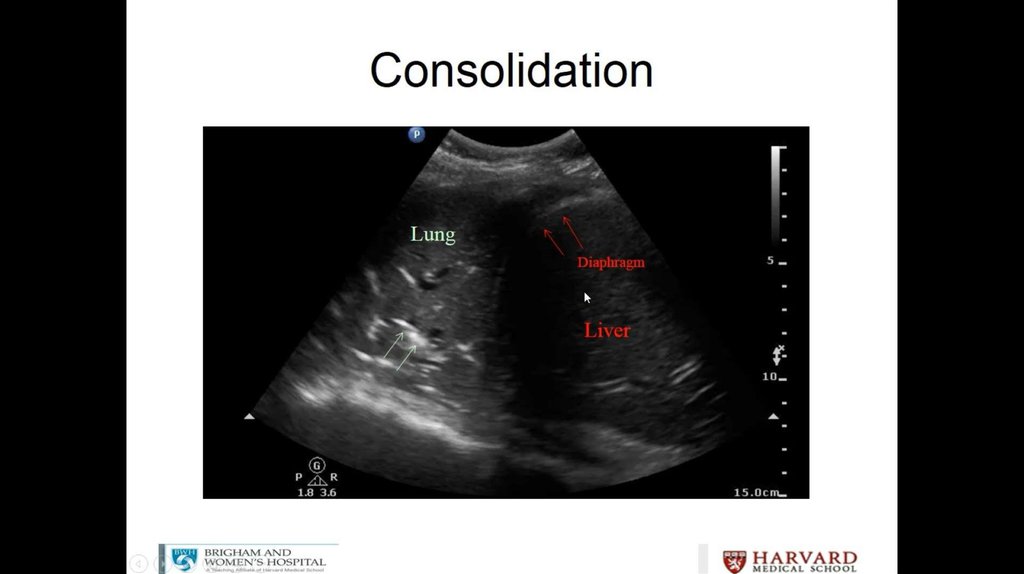

Litrasound in the ICU: What Every Intensivist Should Know